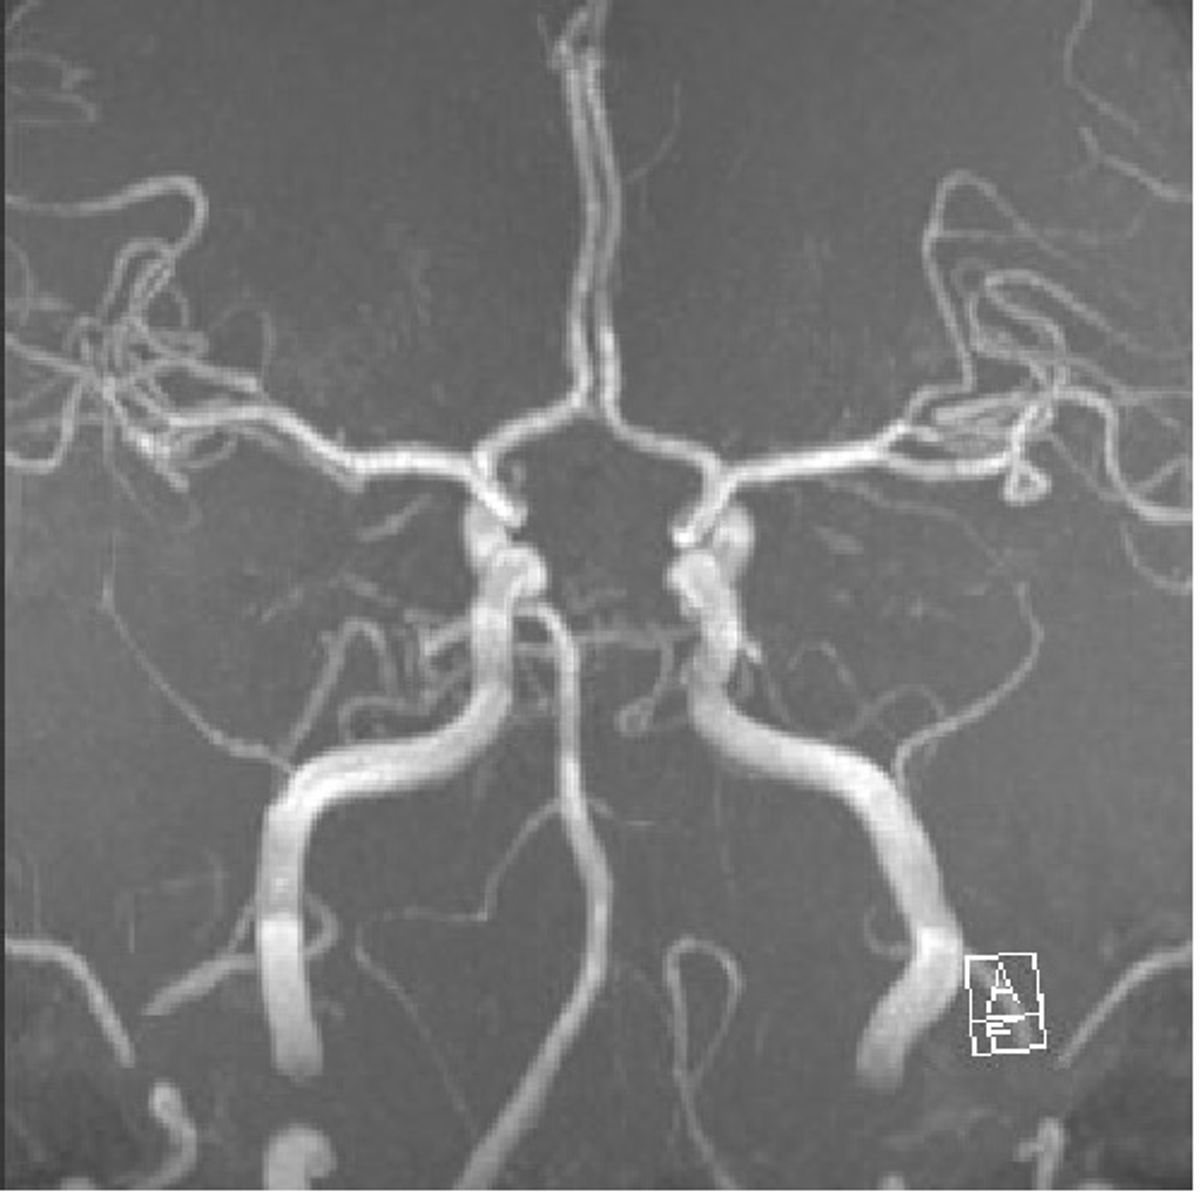

Aneurysmen sind Aussackungen der Gefäßwand, die vor Allem an den Hirnschlagadern durchaus häufig sind - etwa 5% der erwachsenen Bevölkerung tragen ein oder mehrere Aneurysmen in ihrem Kopf.

Die Hauptgefahr geht von einem Riss eines solchen Aneurysmas aus, was zu einer lebensgefährlichen Blutung in die Gehirnhäute oder das Gehirn führen kann (Subarachnoidealblutung).

In Augsburg werden im Jahr etwa 80 solcher akuter Subarachnoidealblutungen behandelt. Dabei ist neben der Behandlung der Blutungsfolgen vor allem die Ausschaltung des ursächlichen Aneurysmas dringlich, was meist interventionell durch die Neuroradiologie erfolgt.

Häufig werden im Rahmen von Untersuchungen des Kopfes Aneurysmen gefunden, die bisher keine Symptome oder gar Hirnblutungen verursacht haben.

Insgesamt behandeln wir etwa 180 Aneurysmen im Jahr.